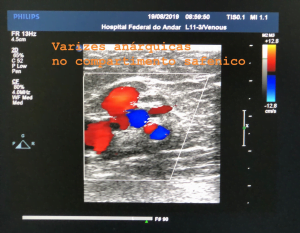

O mapeamento venoso no DUPLEX é utilizado na investigação da doença venosa, por ser sensível, específico e fornecedor de dados anatomofuncionais; facilitando na definição do melhor tratamento e técnica a ser utilizada devido às informações valiosas existentes.

- Sonda de alta frequência de 5 a 8 MHz; linear ou microconvexa para explorar veias profundas e musculares dos membros inferiores.

- Sonda linear de frequência muito alta de 7,5 a 13 MHz para explorar as veias superficiais dos membros inferiores.